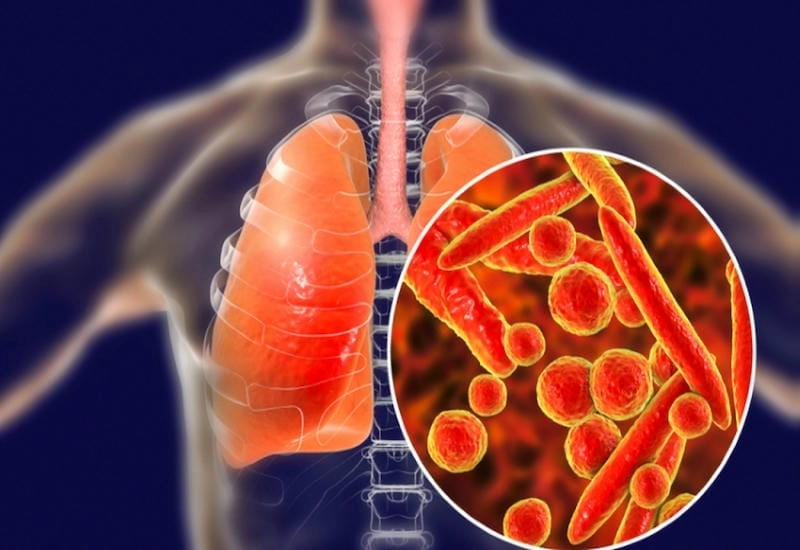

Hình ảnh bệnh lao phổi là tài liệu tham khảo quan trọng giúp người bệnh và bác sĩ dễ dàng nhận biết dấu hiệu bất thường. Việc quan sát hình ảnh X-quang, CT phổi giúp chẩn đoán chính xác mức độ tổn thương và đưa ra phương án điều trị kịp thời.

Bạn sẽ phải rùng mình khi chiêm ngưỡng hình ảnh bệnh lao phổi là như thế nào dưới ống kính y học thực tế. Những bức ảnh chụp X-quang cho thấy phổi bị tổn thương nặng, xuất hiện những đốm trắng mờ như bóng ma ám ảnh. Không chỉ là các tổn thương vật lý, đây còn là những “chứng tích sống” của căn bệnh âm thầm hủy hoại cơ thể qua từng hơi thở. Từ viêm nhẹ đến tổn thương lan rộng, hình ảnh bệnh lao phổi khiến người xem không thể rời mắt vì mức độ nghiêm trọng mà nó thể hiện rõ ràng qua từng chi tiết.

Cảnh báo: tổng hợp ảnh bệnh lao phổi chân thực này không dành cho người yếu tim. Đây là loạt hình ảnh y khoa được các chuyên gia sưu tầm và xác thực, ghi lại quá trình tiến triển của bệnh từ giai đoạn đầu đến giai đoạn nguy kịch. Từng mảng mô phổi bị ăn mòn, xơ hóa, hoại tử được phơi bày rõ nét dưới ánh sáng X-quang lạnh lùng. Những hình ảnh này không chỉ mang tính chất minh họa y học, mà còn là hồi chuông cảnh tỉnh cho bất kỳ ai còn lơ là với căn bệnh nguy hiểm này.

Thông qua những hình ảnh bệnh lao phổi thực tế, người đọc có thể hiểu rõ hơn về diễn biến của bệnh. Việc theo dõi hình ảnh giúp phát hiện sớm, điều trị đúng cách và ngăn ngừa biến chứng nghiêm trọng có thể xảy ra trong tương lai.